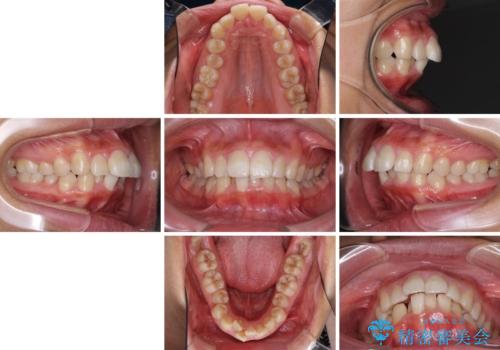

口が閉じられない 抜歯矯正で口元をスッキリと

- 上下の出っ歯を気にして来院された患者様です。

口元を積極的に引っ込めるために、上下左右の第一小臼歯を4本抜歯することとしました。

しっかりと通院するようになってからは順調に治療が進み、横顔の印象が変わるほどスッキリとした口元となりました。